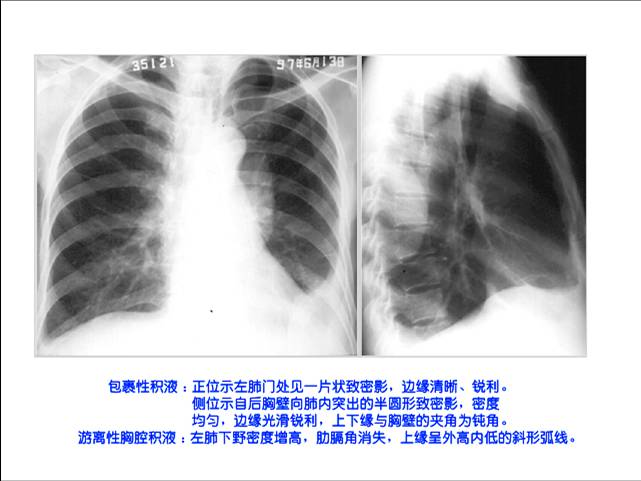

照片名称:胸腔积液

照片名称:左侧胸腔积液

照片名称:左胸腔包裹积液